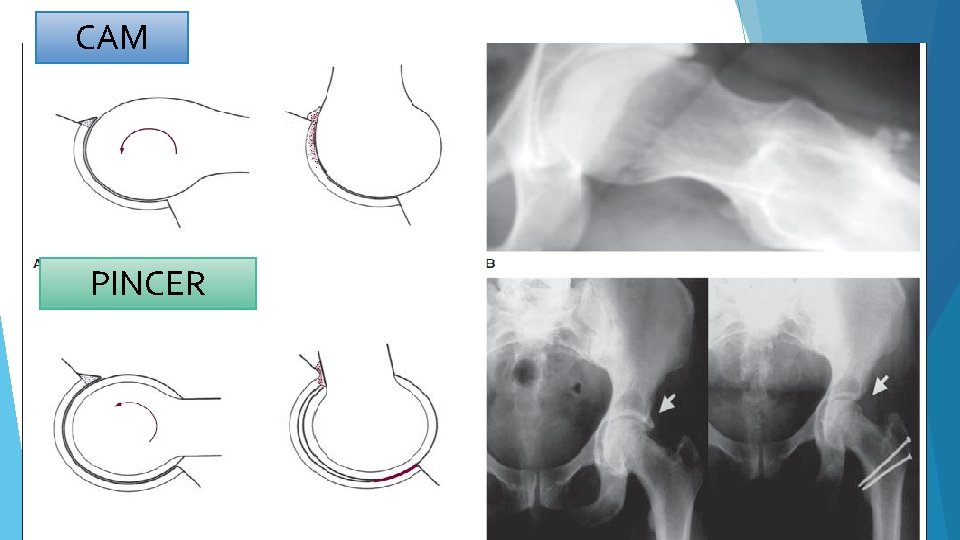

CAM PINCER